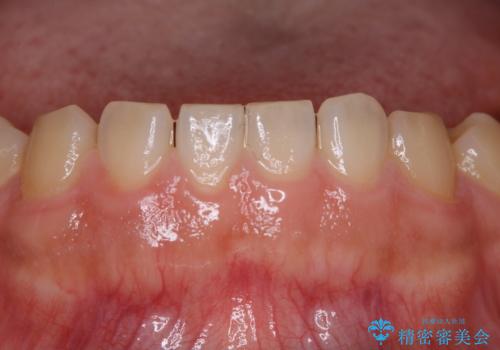

20年ぶりのクリーニングということもあり、歯の表面全てにプラークが付着していました。

プラークの細菌によりかなり歯ぐきが腫れていました。1度のクリーニングで汚れは落とせますが、このまま何もしないとまた同じようにプラークが付着し、それを繰り返すことになるだけでなく、歯周病や虫歯が進行してしまいます。そうならないためには、日々のケア、ホームケアがとても大事になっていきます。